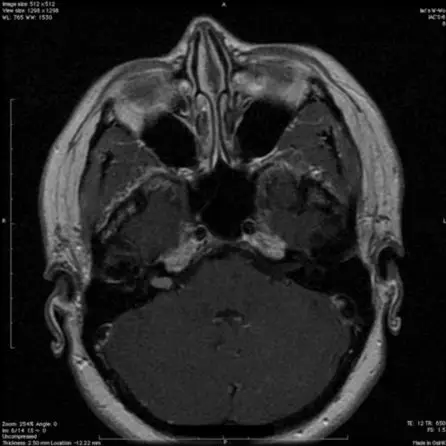

19.特发性颅内高压患者腰椎穿刺大量放液后静脉窦狭窄瞬时缓解

Transient resolution of venous sinus stenosis after high-volume lumbar puncture in a patient with idiopathic intracranial hypertension

PMID: 28841117 DOI: 10.3171/2017.3.JNS163181

横窦(transverse sinus,TS)和乙状窦(sigmoid sinus, SS)狭窄已运用于特发性颅内高压(idiopathic intracranial hypertension, IIH)患者的病理生理学研究。IIH患者行腰椎穿刺大量释放脑脊液(high-volume lumbar puncture, HVLP)后,MRI显示TS和SS狭窄改善,血管内超声成像(intravascular ultrasonography, IVUS)显示TS和SS的横截面积随之增加。TS-SS反复狭窄患者与HVLP颅内压开放压力升高相一致,静脉窦支架放置可以改善患者的临床预后。研究指出,TS和SS狭窄可能是IIH患者颅内压升高的下游效应,而不是其主要病因学机制。

【李信晓】